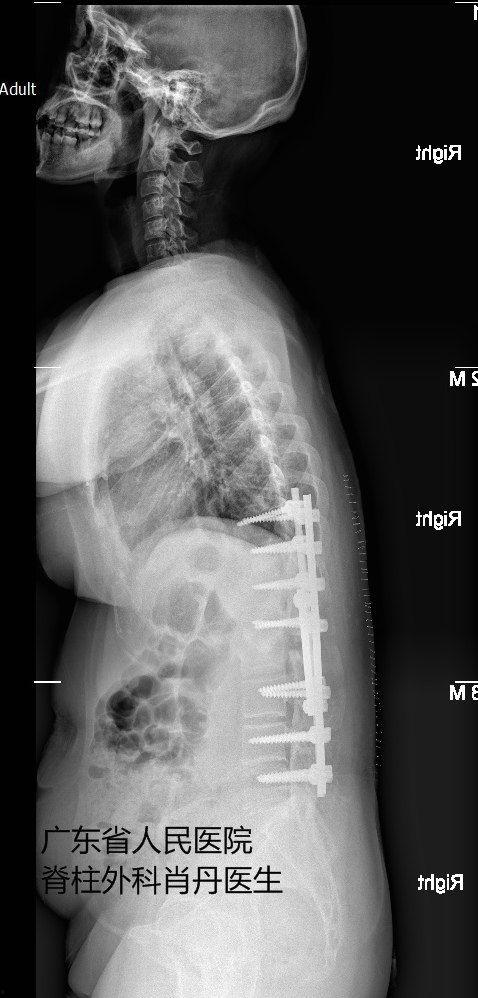

手术过程中,医生会根据患者的具体情况,选择合适的手术方式。常见的手术方法有:脊柱融合术、脊柱截骨术、脊柱侧弯矫正术等。这些手术都需要在全身麻醉下进行,患者将在无知觉的状态下完成这场与病痛的较量。